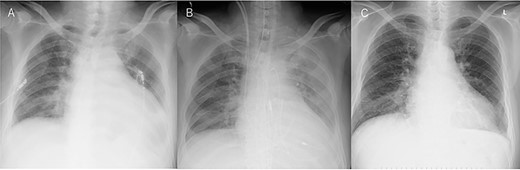

An Asian male in his 60s complained of sudden chest pain and was referred to a regional hospital. Electrocardiography showed massive ST-elevation in V1-4, and emergency coronary angiography revealed occlusion of the left anterior descending (LAD) artery (Fig. 1a). PCI was successfully performed (Fig. 1b), and IABP was inserted. Maximum value of creatine-kinase was 10 080Â U/l, and his left ventricular function was severely impaired with an ejection fraction of 30%. High dosage of catecholamine was administrated and his hemodynamic status gradually recovered; however, he fell into profound cardiogenic shock on post PCI Day 6. Chest X-ray showed significant cardiomegaly (Fig. 2a), and trans-thoracic echocardiography revealed cardiac tamponade.

Chest X-ray findings. (A) Preoperative, (B) immediately after operation and (C) just after explantation of Impella.

The patient was transferred to our hospital where emergency operation was performed via median sternotomy. Oozing type LVFWR on the anterior wall was found, and was treated with a non-suture technique using TachoSil (Nycomed, Zurich, Switzerland), and without cardiopulmonary bypass. Thereafter, the IABP was removed and Impella CP was inserted percutaneously from the right groin (Fig. 2b). His hemodynamic condition recovered dramatically, and the Impella was removed on postoperative Day 5 (Fig. 2c). The patient was discharged home on postoperative Day 18, and 3Â months after the onset of MI, he is doing well.